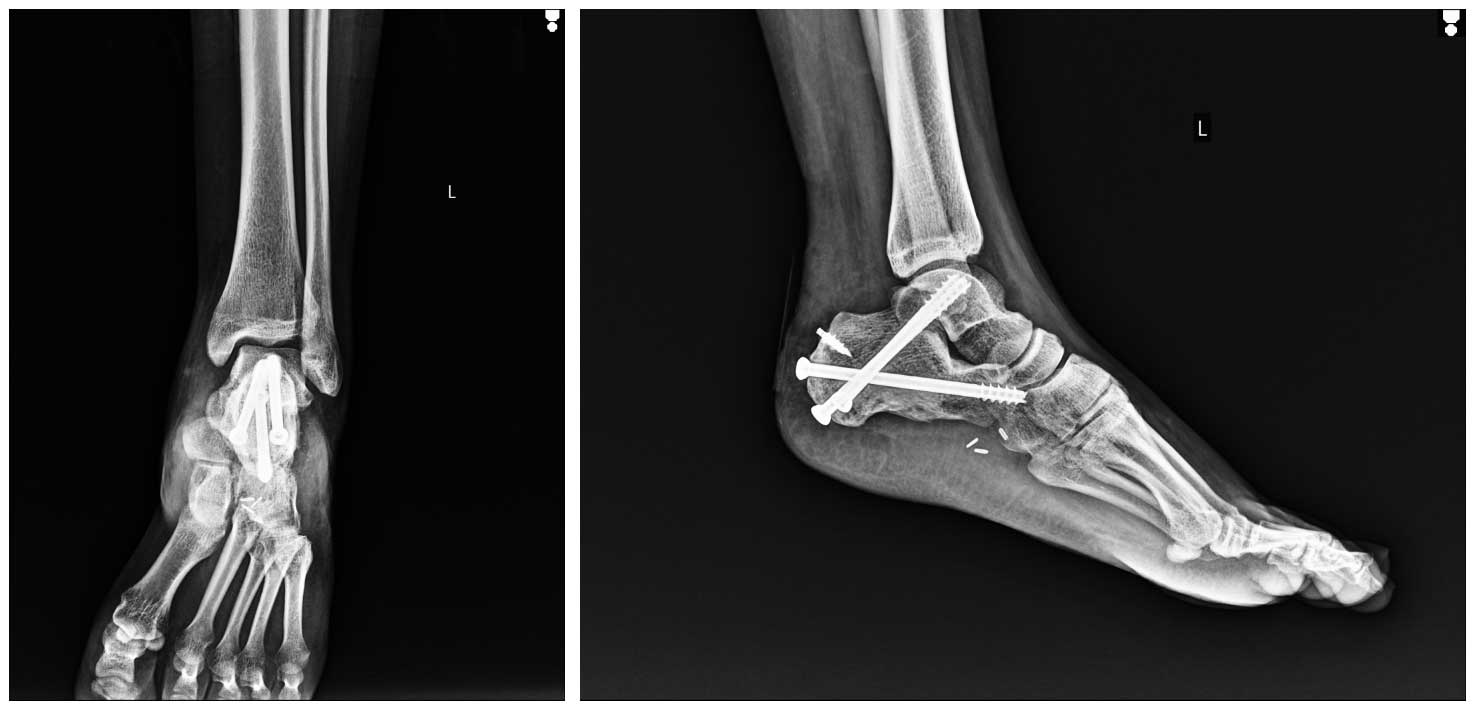

Ameliyat Esnası: Sıvı azot ile geri kazanım sonrası Kalkaneus’ta oluşan boşluğun çimento ile doldurulmasını takiben önce geçiçi K telleri ile sonra kanüle vidalar ile artrodez işleminin yapılması.

Ameliyat Sonrası: Röntgende geri kazanılıp içi çimento ile doldurulan Kalkaneus’un kanüle vidalar ile artrodez yapılması ve aşil tendon stürü için anchor yerleşimi görülmekte.